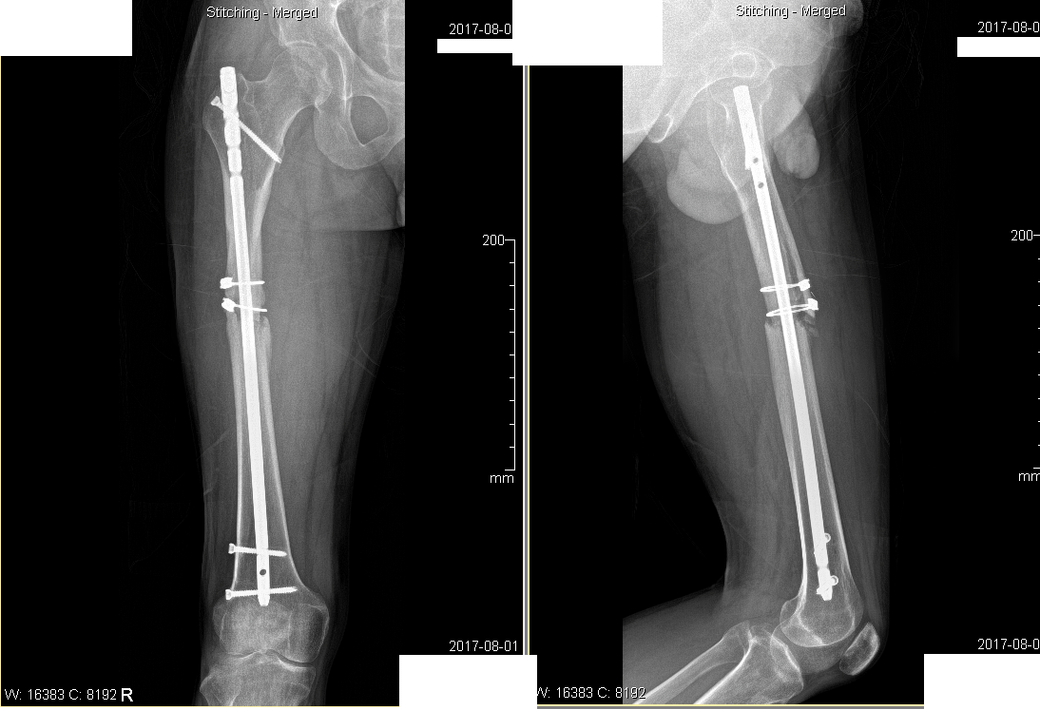

2016년 11월 대퇴부골절

2017년 / 2020 년 사진입니다.

• 1번 째 사진

사진으로도 약간은 어긋난 상태로 아문 것이 사실이지만 이미 시간이 5년이

2. 엑스레이상 보면 대퇴골 중간에 불유합부위가 보이는데 이로 인해 대퇴골이 일직선이 아니고 삐뚤어져있습니다. 이게 통증을 유발하는지는 정형외과 선생님에게 물어보셔야겠습니다.